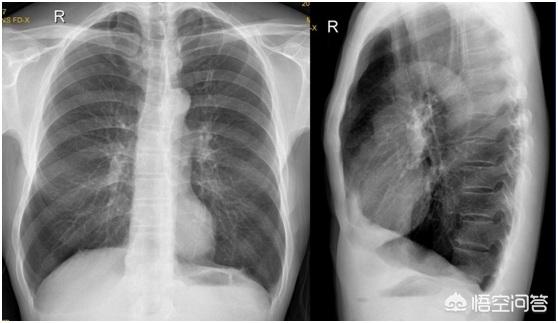

Présentation radiographique : ① le diamètre antérieur et postérieur de la cage thoracique est élargi en forme de tonneau, et l'espace intercostal est élargi. La position du sommet du diaphragme des deux côtés diminue et le sommet du diaphragme devient plat. La translucidité des poumons augmente et la texture des poumons devient mince, allongée et redressée. ④ Sous fluoroscopie, la motilité des deux diaphragmes est affaiblie. ⑤ L'emphysème interstitiel est souvent présent dans le médiastin, le péricarde et le tissu sous-cutané. (6) Un pneumothorax confiné et une atélectasie pulmonaire peuvent se produire dans les alvéoles rompues.

Chez de nombreux fumeurs âgés, le médecin dira, après une radiographie du thorax, qu'il s'agit d'un emphysème. Le fait que la radiographie du thorax permette de voir deux poumons est en effet un signe d'emphysème, l'ensemble du thorax est gonflé, comme un seau, d'où le nom de "thorax en seau". Dès que nous, médecins, voyons la poitrine du patient, pleine, combinée à des antécédents de tabagisme, nous savons que cette personne peut souffrir d'emphysème.